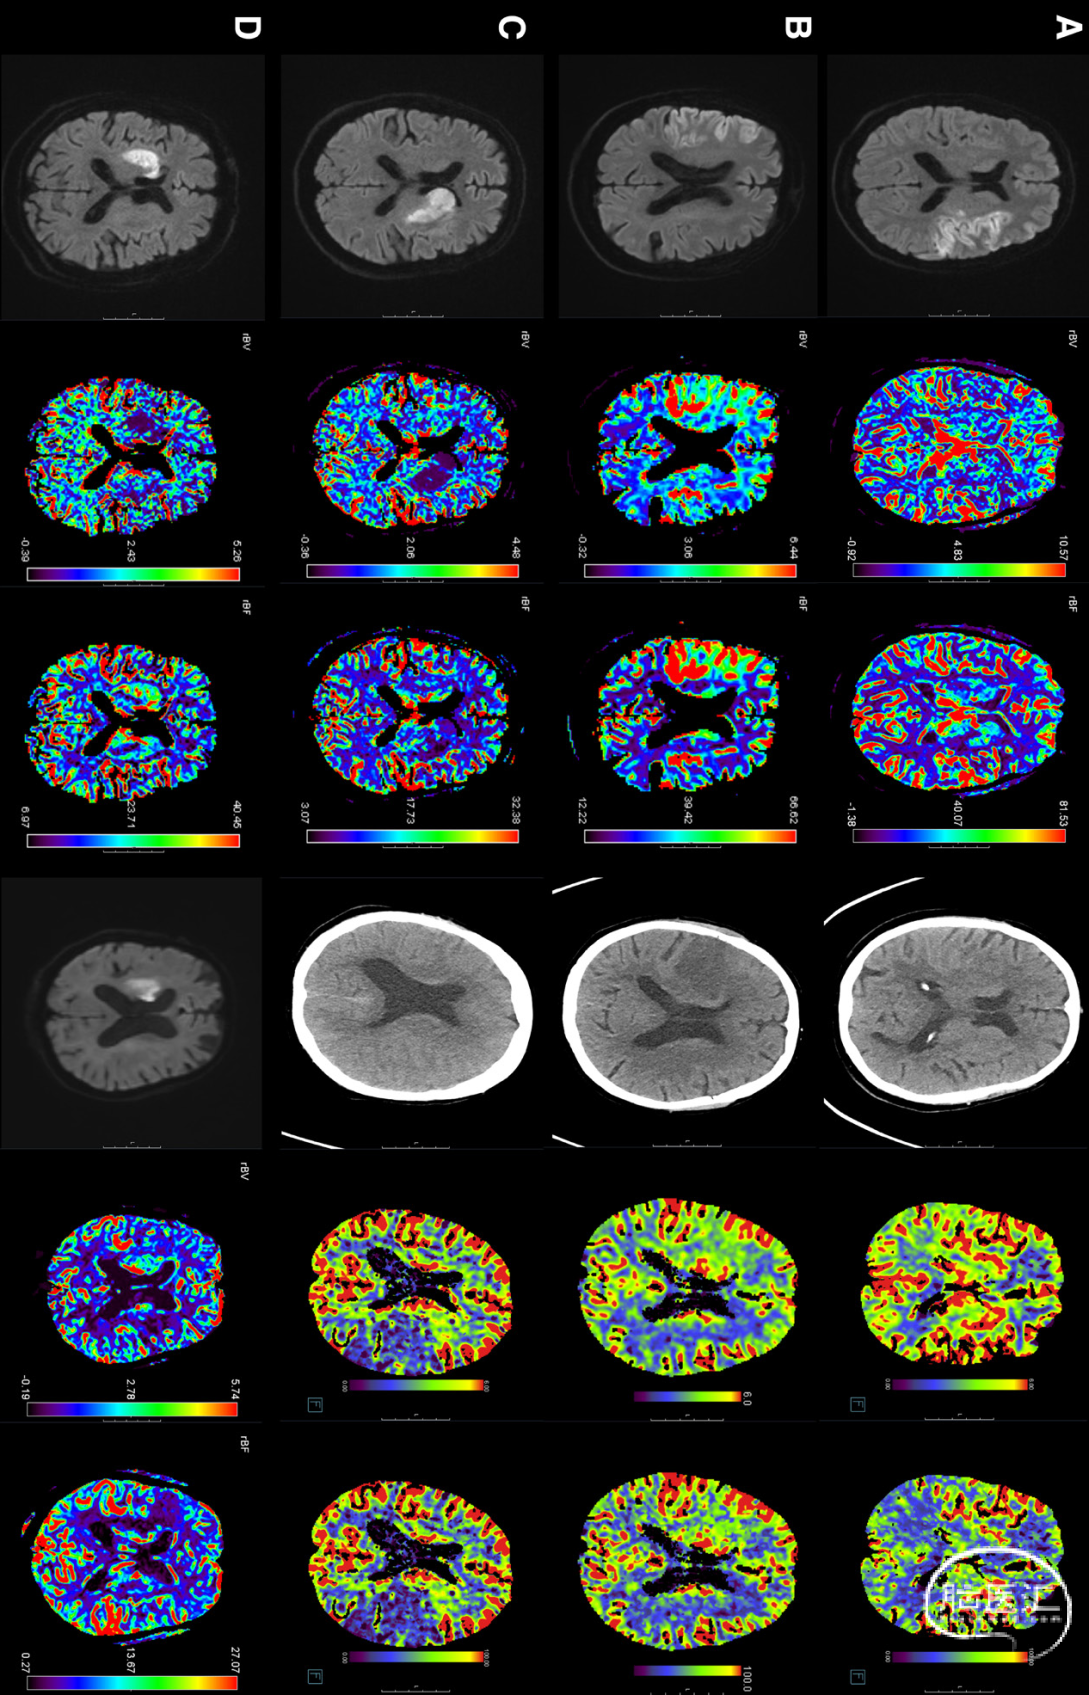

根据微血管灌注结果,整个队列(N=248,译者注:这248例皆达到了TICI 3)分为4组:(1)正常灌注(无灌注异常;N=143/248);(2)高灌注(脑血容量和脑血流量均高灌注;n=54/248);(3)低灌注(脑血容量和脑血流量均低灌注;n=14/248);和(4)混合(不同的发现,例如,脑血容量低灌注和脑血流量高灌注;n=37/248)。

图1.患者组。A,正常灌注,左右分别为两位不同的患者。B,高灌注。C,低灌注。D,混合:

与正常灌注组相比,低灌注组患者实现功能独立的可能性较低(调整后的比值比为0.3[95%CI,0.1-0.9]),而高灌注组患者的预后往往更好(调整后比值比为3.3[95%CI、1.3-8.8])。